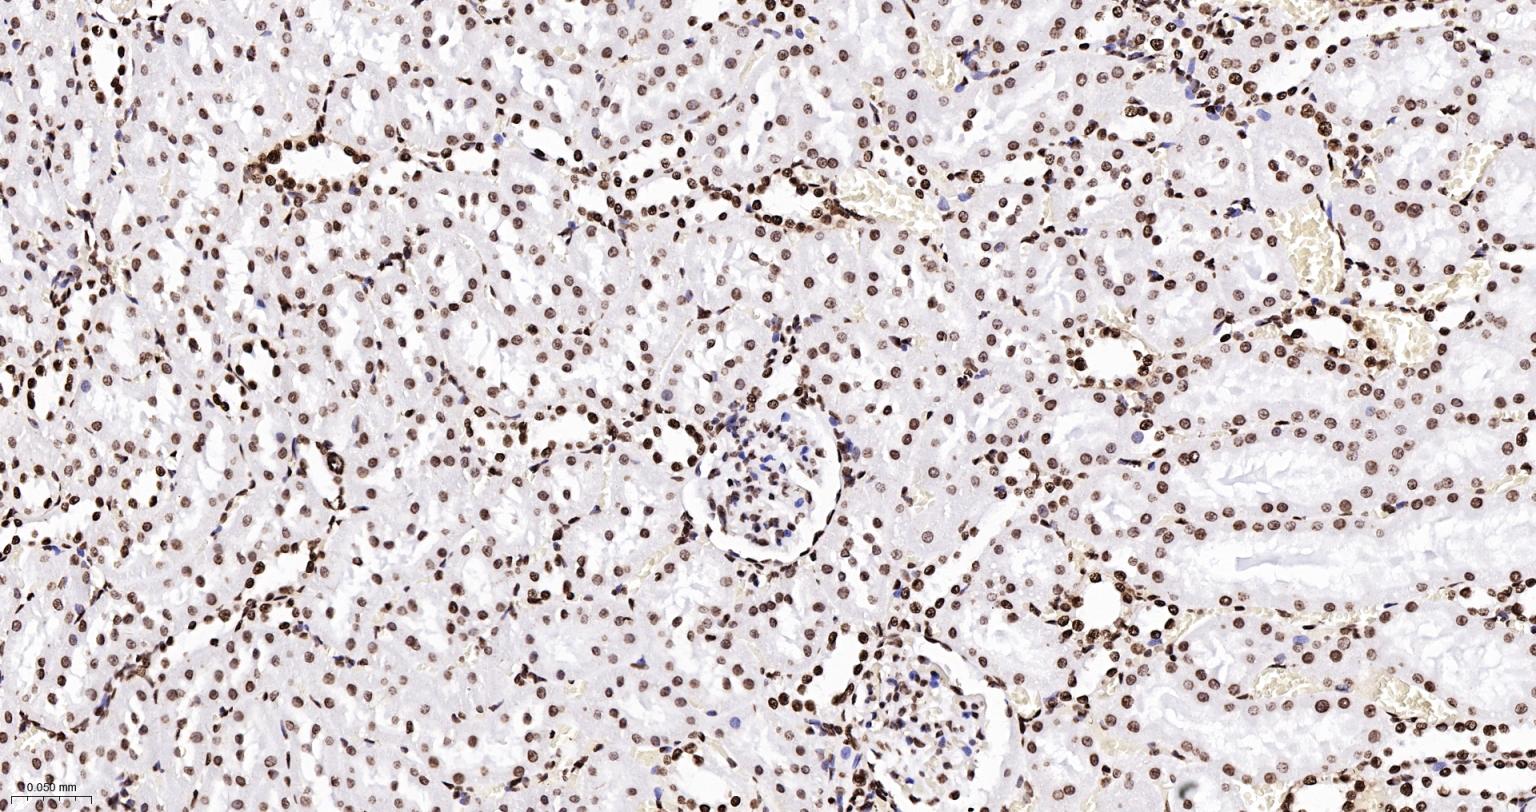

Paraformaldehyde-fixed, paraffin embedded Human Kidney; Antigen retrieval by boiling in sodium citrate buffer (pH6.0) for 15 min; Antibody incubation with Histone H2A.X Monoclonal Antibody, Unconjugated(bsm-61080R) at 1:200 overnight at 4°C, followed by conjugation to the SP Kit(Rabbit, SP-0023) and DAB (C-0010) staining.